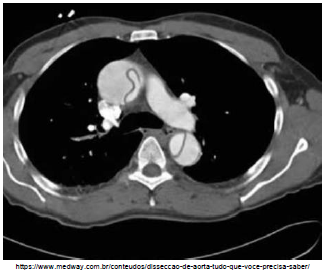

Analise a imagem a seguir.

Essa dissecção apresentada na imagem acima é tipo